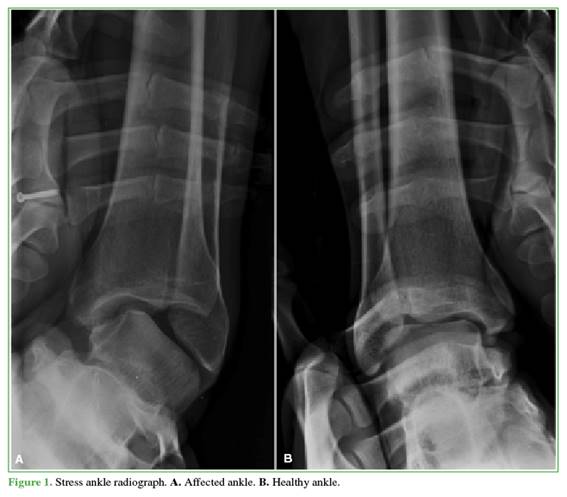

To assess repair of the lateral ligament complex, a stress radiograph was obtained six months after surgery (Figure 3). For clinical-functional evaluation, the AOFAS scale (American Orthopaedic Foot and Ankle Score) and the Visual Analog Scale (VAS) were used.